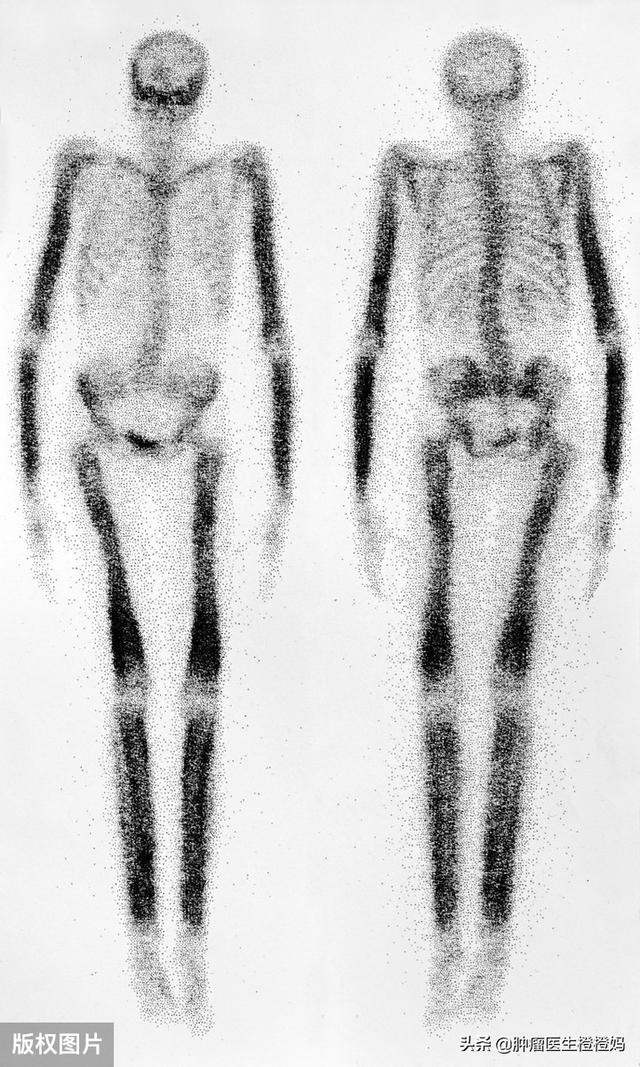

- 全身骨スキャン:骨転移の有無を最初に判定する主要な手段であり、一般に一次スクリーニングとして使用されます。そのため、悪性腫瘍と診断されると、主治医から骨スキャンを受けるよう勧められます。全身をくまなく掃除する。.しかし、骨スキャン上の炎症反応の一部は骨転移のものと似ているため、診断の補助としてさらにX線、CT、MRが必要である。

骨転移の最も一般的な検査は骨核種スキャンで、これは費用が安く、X線、CT、MRIなどの画像検査でさらに確認された問題を明らかにする。もちろんPET-CTは骨核スキャンより優れているが、費用が高すぎる。

第二に、検査の結果に基づいている。癌の骨転移は、画像上、造骨性または溶骨性破壊として現れる。これは通常の骨病変とは大きく異なります。臨床的には、骨転移の有無を判断するために骨シンチを用いるのが一般的です。👆👆👆上图中,特别'黑'的地方可能就是骨转移!もちろん、他の検査で原発巣が見つからなければ、医師は骨転移が疑われるこの部位の骨組織の病理検査を選択することもあります。ひとつは本当に悪性腫瘍の骨転移なのかを判断すること、もうひとつは病理染色によってがん細胞がどこから発生したのかを判断することです。